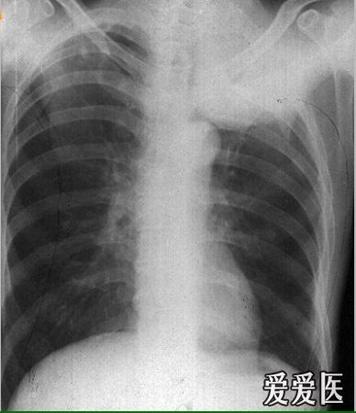

肺上沟癌

肺上沟癌,肺癌患者的肺